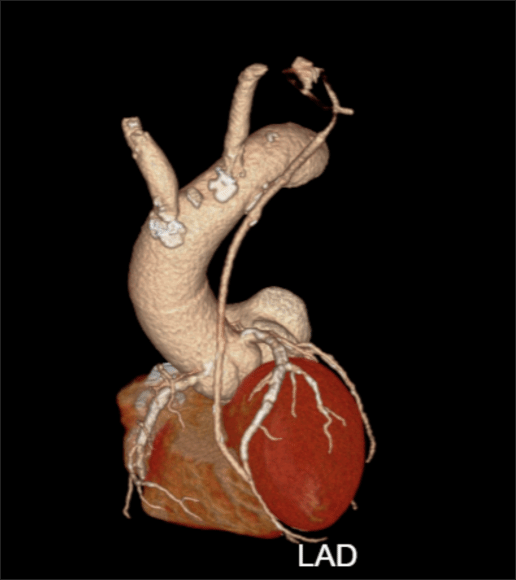

左图:术前冠脉造影(白色箭头指示前降支支架内严重狭窄) 右图:术前CT影像(双肺肺气肿、肺大疱)

术后复查冠脉CT显示桥血管通畅